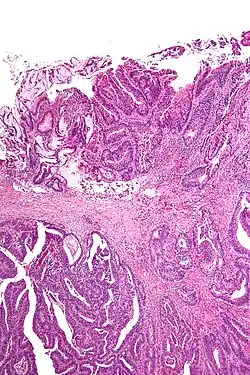

Micrograph showing a positive cauterized surgical margin in an adenocarcinoma (center-top of image). H&E stain.